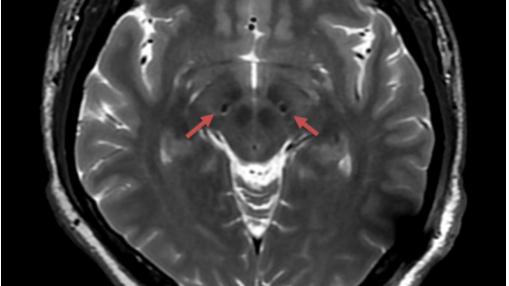

周洪語功能團隊進行了充分評估后,決定為陳先生選擇植入國產(chǎn)新型腦起搏器(3.0T磁共振兼容腦起搏器)。腦起搏器療法將電極植入到大腦深部神經(jīng)核團,通過電刺激調(diào)節(jié)神經(jīng)環(huán)路的異常電活動,緩解運動障礙癥狀,使患者恢復活動能力。

據(jù)悉,腦起搏器經(jīng)過多次更新迭代,傳統(tǒng)腦起搏器使用期限為20年,并容易受到磁場的干擾而發(fā)生風險,故而被禁止在開機狀態(tài)下接受高場強3.0T磁共振掃描。過去,植入腦起搏器的患者僅可接受局限的1.5T磁共振掃描,同時必須關(guān)掉腦起搏器。陳先生還年輕,未來也許還要接受磁共振檢查,尤其是3.0T磁共振檢查的機會較多,長達30年預期使用期限的國產(chǎn)新型腦起搏器更適合他。

手術(shù)中,功能團隊和影像科、麻醉科密切配合,高清結(jié)構(gòu)影像定位、術(shù)中微電極記錄和術(shù)中CT驗證,一氣呵成,電極精準植入。